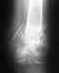

Здравствуйте!По заключению из ГУ РНИИТО им. Р.Р.Вредена у меня имеется (обнаружилось после разрыва внешних (латеральных) голеностопных связок) :

: "в верхнем передне-наружном отделе блока правой таранной кости определяется дефект суставной поверхности, размерами 1.3х1.1.7х0.5 см, ограниченный зоной резорбции шириной до 0.6см с наличием свободного внутрисуставного тела размерами 0.8х0.5х0.3см. В полости сустава определяется избыточное количество жидкости.Заключение: Асептический некроз передне-наружного отдела блока правой таранной кости. Синовит"снимки при необходимости добавлю.мне тогда сказали (июль 2008 года), что необходима операция, ибо я не буду ходить, но я не стал ее делать. Жидкость наблюдается вокруг сустава до сих пор!боли периодически возникают. Спортом заниматься толком не позволяют. мне 19 лет, операцию делать не хочется, ведь у многих после операции продолжает скапливаться жидкость, например, или дальше болит сустав...помогите, я растерян. у меня даже нет освобождения от армии, в таком-то положении.